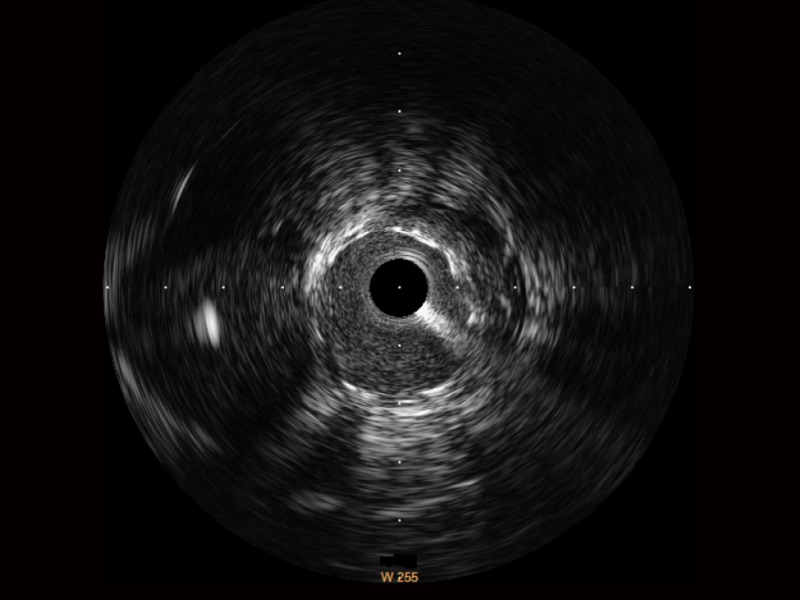

• 传统IVUS图像

对比传统IVUS导管成像,milan米兰宽频IVUS图像的近场支架梁显影更细腻,远场中膜外血管仍清晰可辨,兼顾远中近,兼顾分辨力与穿透深度